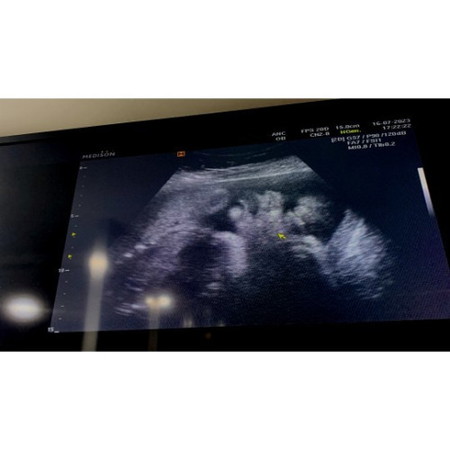

มาอวดเจ้าก้อนกันเถอะ 🤰🏻🤍🥰

บ้านนี้ 31+6 w🤰🏻 น้องหนัก 1,700 กรัม🛎️ แล้วครับ บ้านอื่นหนักกันเท่าไหร่แล้วครับ ❤️✨🌻#ขอบคุณสำหรับคำตอบค่ะ #ขอคำแนะนำหน่อยค่ะ #ท้องแรกคะ #ขอบคุณล่วงหน้านะคะ #คุณแม่ๆช่วยแนะนำหน่อยค่ะ